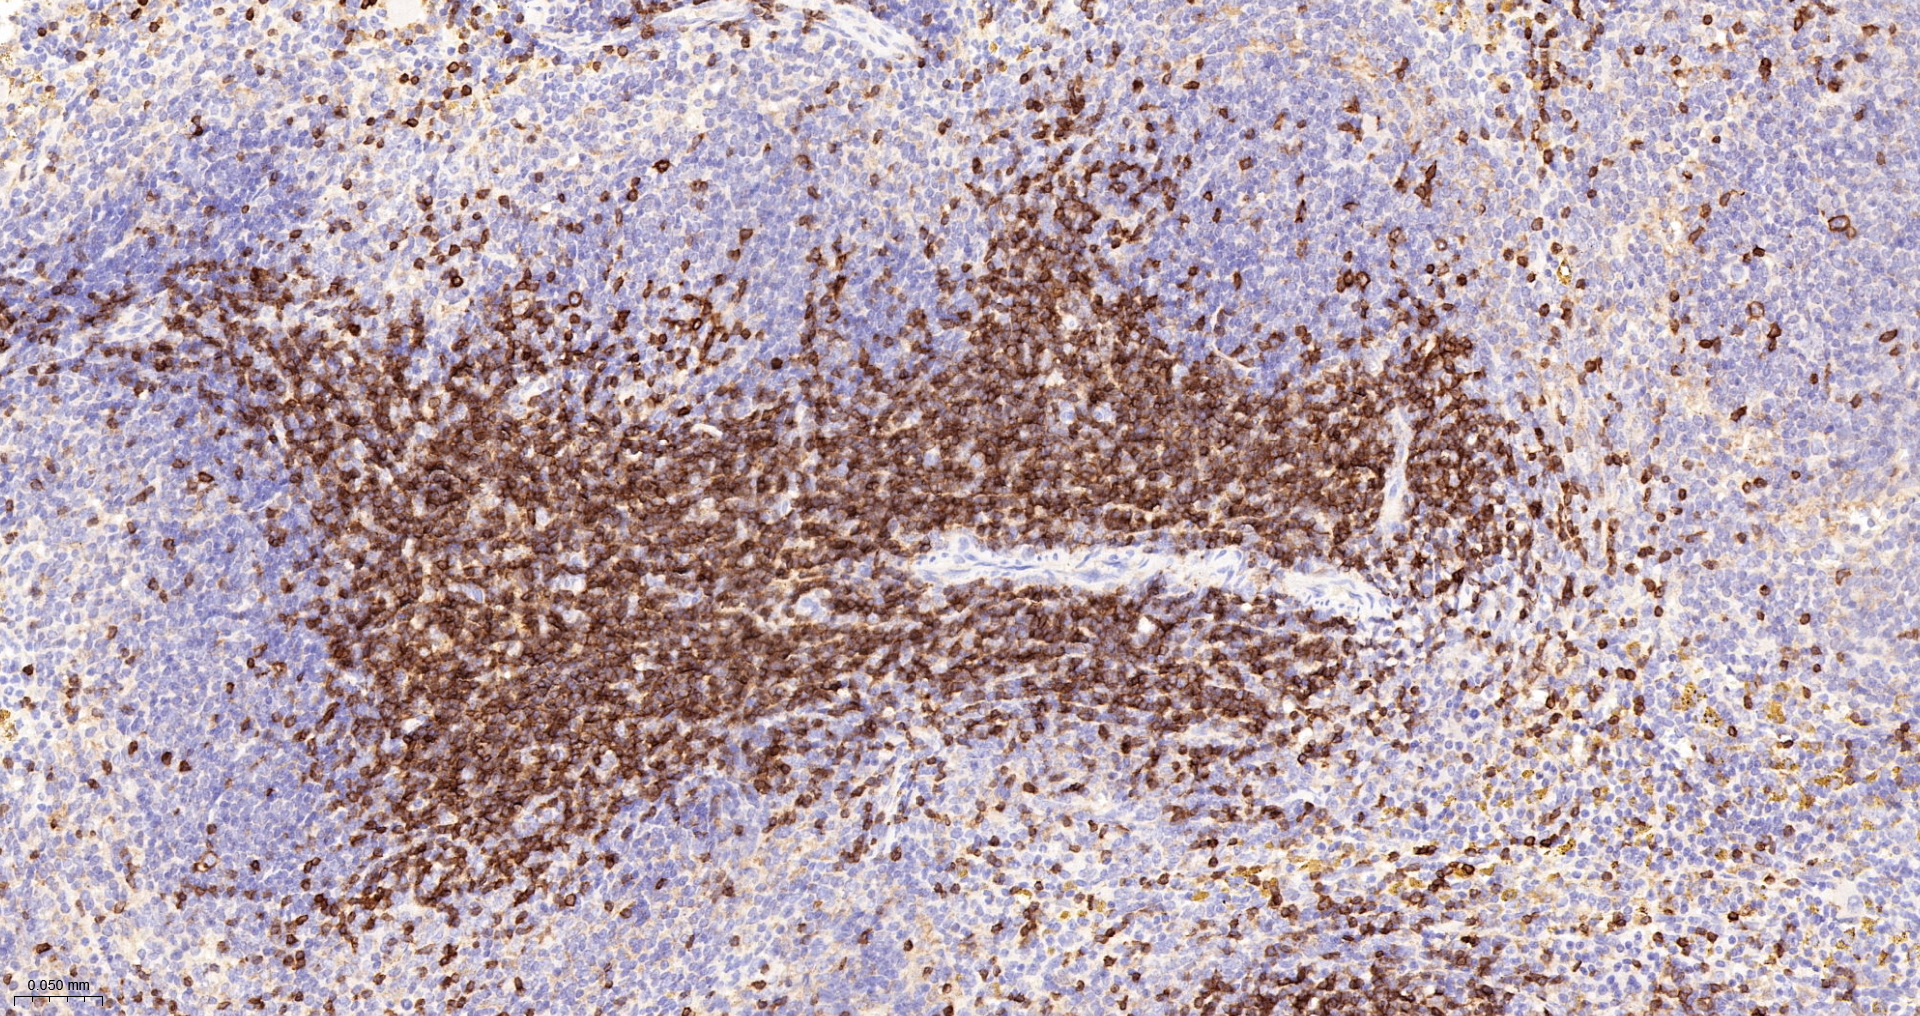

| IHC-P |

1:500-1000 |